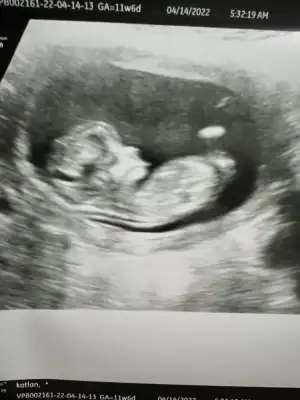

ilk foto kız ikinci foto hala erkek gibi. Baksana kuzuum ilkinde bebeğin uzandığı yer paralel düz gibi , ikincisinde yukarı kayan bir şekli var. Keşke doktorlar gibi bizde hareketli anlarına baksak. Doktlar bence 13 haftalarda cinsiyet söyleyebilir ama korkuyorlarSelamlarrr yine benBu kez 11+6 usg görüntüsüyle geldim tekrar bakarsanız çok sevinirim

![]()